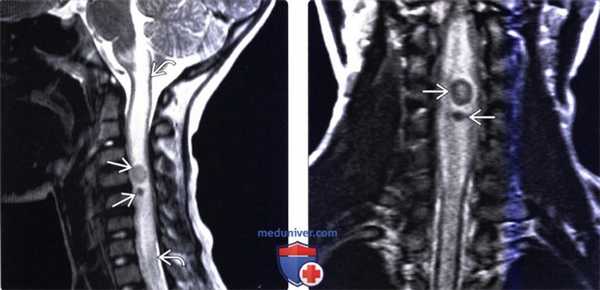

(Слева) Сагиттальный срез, Т1-ВИ с КУ: контрастирующееся по периферии очаговое кистозное образование спинного мозга, сопровождающееся веретеновидным утолщением спинного мозга на этом уровне. Интрамедуллярные очаги составляют 20% случаев СЦЦ. Наиболее вероятным путем развития интрамедуллярного СЦЦ является гематогенная диссеминация.

(Справа) Аксиальный срез, Т1-ВИ с КУ: интрамедуллярная контрастирующаяся по периферии цистицеркоидная киста дистальной части грудного отдела спинного мозга. Киста сопровождается веретеновидным утолщением спинного мозга.

(Слева) Сагиттальный срез, Т2-ВИ: диффузное увеличение объема и гиперинтенсивность сигнала шейного отдела спинного мозга. В толще спинного мозга видны два гипоинтенсивных очага. Распространенный отек спинного мозга наблюдается при коллоидной и гранулярно-нодулярной стадиях СЦЦ и связан с высвобождением продуктов метаболизма паразита. Стенки кист на этих стадиях выглядят утолщенными и гипоинтенсивными.

(Справа) На данном фронтальном Т2-ВИ видны две интрамедуллярные цистицеркоидные кисты, сопровождающиеся выраженным отеком окружающей паренхимы спинного мозга. Отмечается веретеновидное утолщение спинного мозга на уровне поражения.